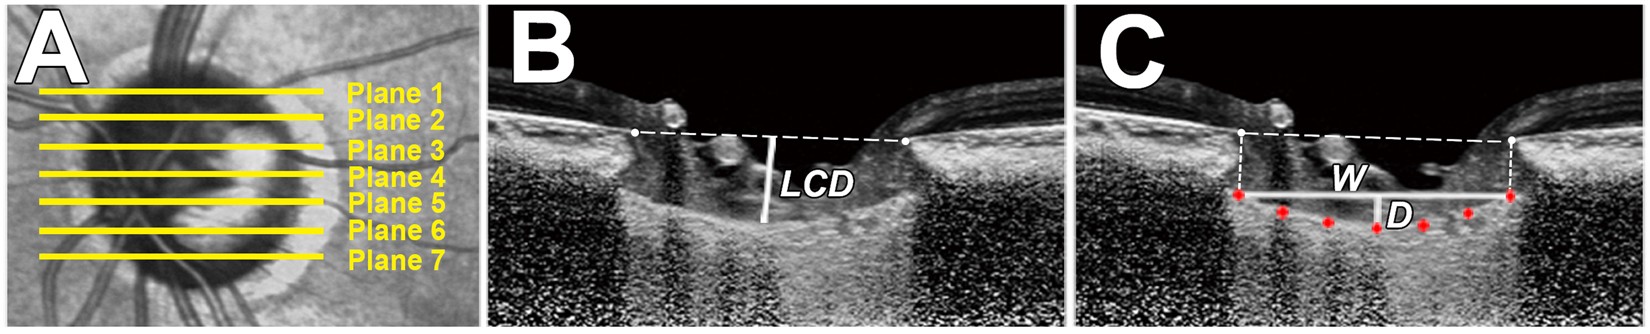

Figure 5

Measurement of the lamina cribosa depth (LCD) and lamina cribrosa curve index (LCCI) using B-scan images of the optic nerve head. (A) Infrared fundus image with lines pointing to the level of seven B-scan images spaced equidistantly across the vertical optic disc diameter in each eye. (B) The LCD was measured as the distance from the reference line connecting the two Bruch’s membrane opening (BMO) points to the anterior surface of the lamina cribrosa (LC). The LCD was measured at the maximally depressed point. (C) The LCCI was measured by dividing the LC curve depth (D) within the BMO by the width of the anterior LC surface reference line (W), and then multiplying by 100.